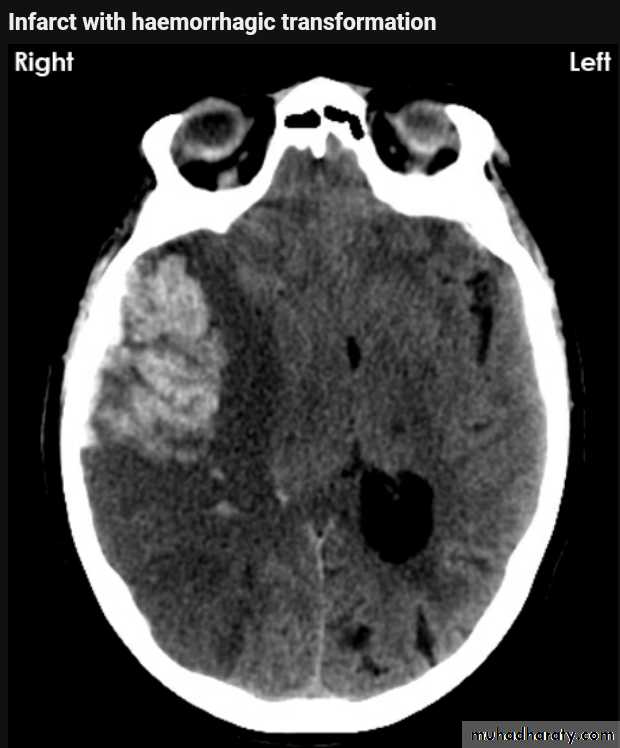

Infarction

AcuteChronic

Acute infarction

Wedge shape area of hypo density involve the tributaries of anterior , middle or posterior cerebral arteries , ( i.e. priato frontal &priato occipital area )

Dense middle artery sign

* wedge shape hypo density area.* Shifting of the midline & frontal horn

Chronic infarction

Hypo density area(pore encephalic cyst)Dilated ventricle